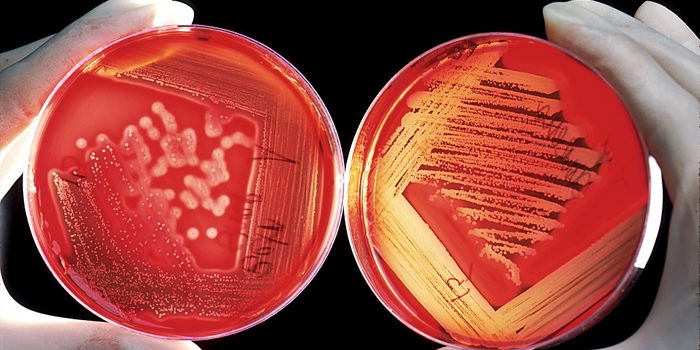

AUG 20, 2016Clinical & Molecular DXCan the staph superbug, also known as MRSA, be brought down by salt? Scientists finally expose a key weakness in these b ...